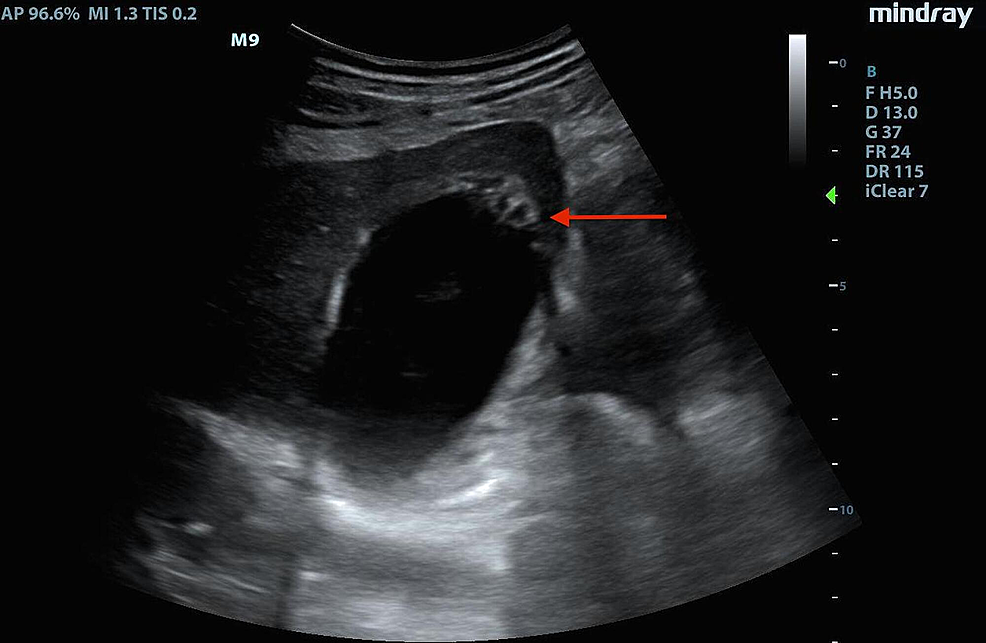

Abdominal ultrasound reveals a distended gallbladder (9 × 3.8 cm) with What Is The Normal Thickness Of The Bladder Wall It is not uncommon to see a thickened urinary bladder wall in cases of chronic bladder outlet obstruction. 1 mm in normal adult men. This thickening can be detected. Bladder wall thickening refers to a condition in which the bladder walls become denser than normal. Bladder wall thickening (bwt) is not a specific condition but an indication of the potential. What Is The Normal Thickness Of The Bladder Wall.